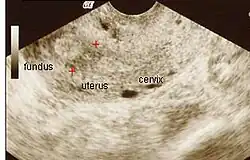

Im Ultraschall lassen sich Hinweise auf das Krankheitsbild finden. Das Endometrium lässt sich meist nur mit Schwierigkeit identifizieren. Je nach Lokalisation der Verwachsungen kann ggf. auch eine Hämatometra darstellbar sein.

Im Vergleich zur Hysteroskopie, welche heute die Standardmethode zur Diagnostik darstellt, hat die transvaginale Sonografie jedoch nur eine Sensitivität von 52 % und eine Spezifität von 11 % beim Nachweis von intrauterinen Verwachsungen.[4] In der dreidimensionalen Ultraschalluntersuchung (3D-Sonografie) zeigt sich in den betroffenen Bereichen ein vermindertes Endometriumvolumen.[7]

Vor einem Eingriff spielt die Transvaginalsonographie dennoch eine wichtige Rolle. Patientinnen, bei welchen ultrasonographisch hinter einem obstruktiven Bereich Endometrium nachgewiesen werden kann, haben eine größere Wahrscheinlichkeit erfolgreich behandelt zu werden.[4] Die Gebärmutterspiegelung kann im Vergleich zu allen anderen Verfahren viel genauer und präziser Vorhandensein, Ausmaß und Grad von intrauterinen Adhäsionen darstellen und ermöglicht eine gute Beurteilung der Qualität des restlichen Endometriums. Sie gilt daher als Methode der Wahl bei der Diagnostik von intrauterinen Adhäsionen.